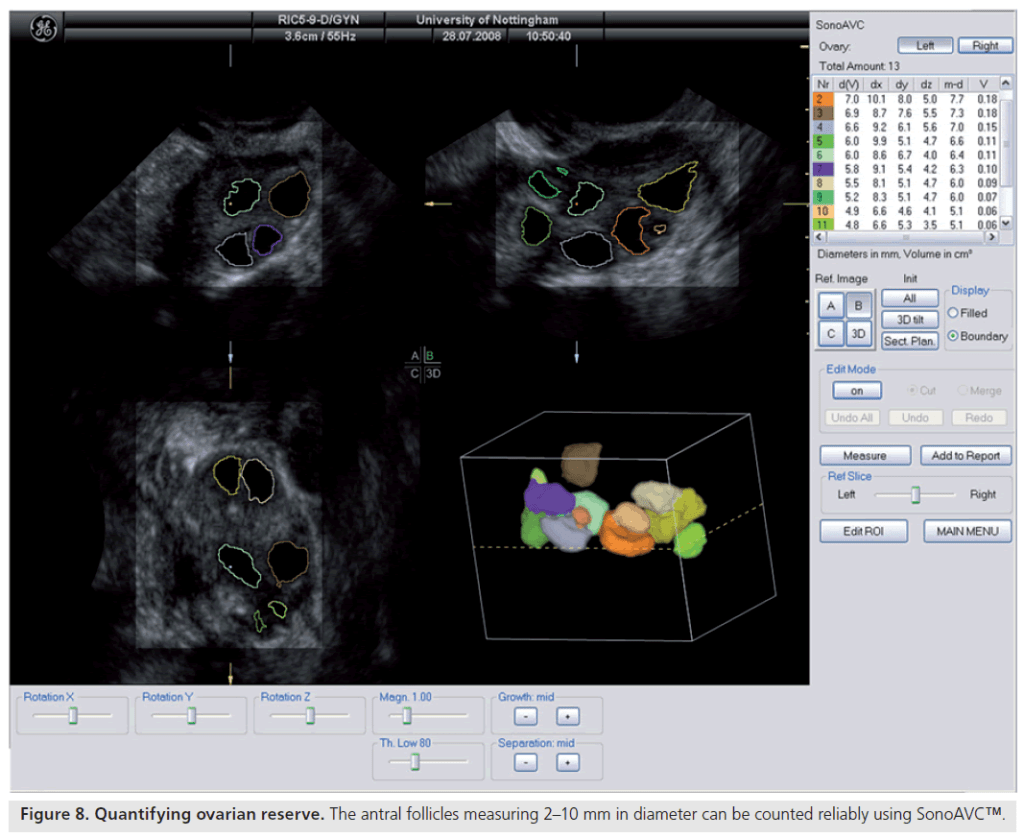

Entre os métodos ultrassonográficos disponíveis, considera-se a contagem de folículos antrais (AFC) o marcador mais confiável para estimar a reserva ovariana.

Realizada por meio de ultrassonografia transvaginal, ela quantifica os folículos de 2 a 10 mm presentes em ambos os ovários, podendo ser feita em 2D ou 3D. As tecnologias tridimensionais e as ferramentas automatizadas, como o SonoAVC, oferecem medições mais precisas e reprodutíveis.